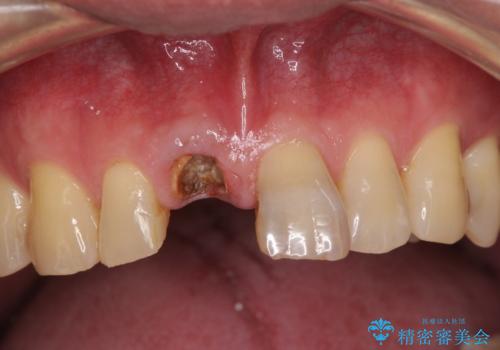

折れてしまった前歯 インプラントによる補綴治療